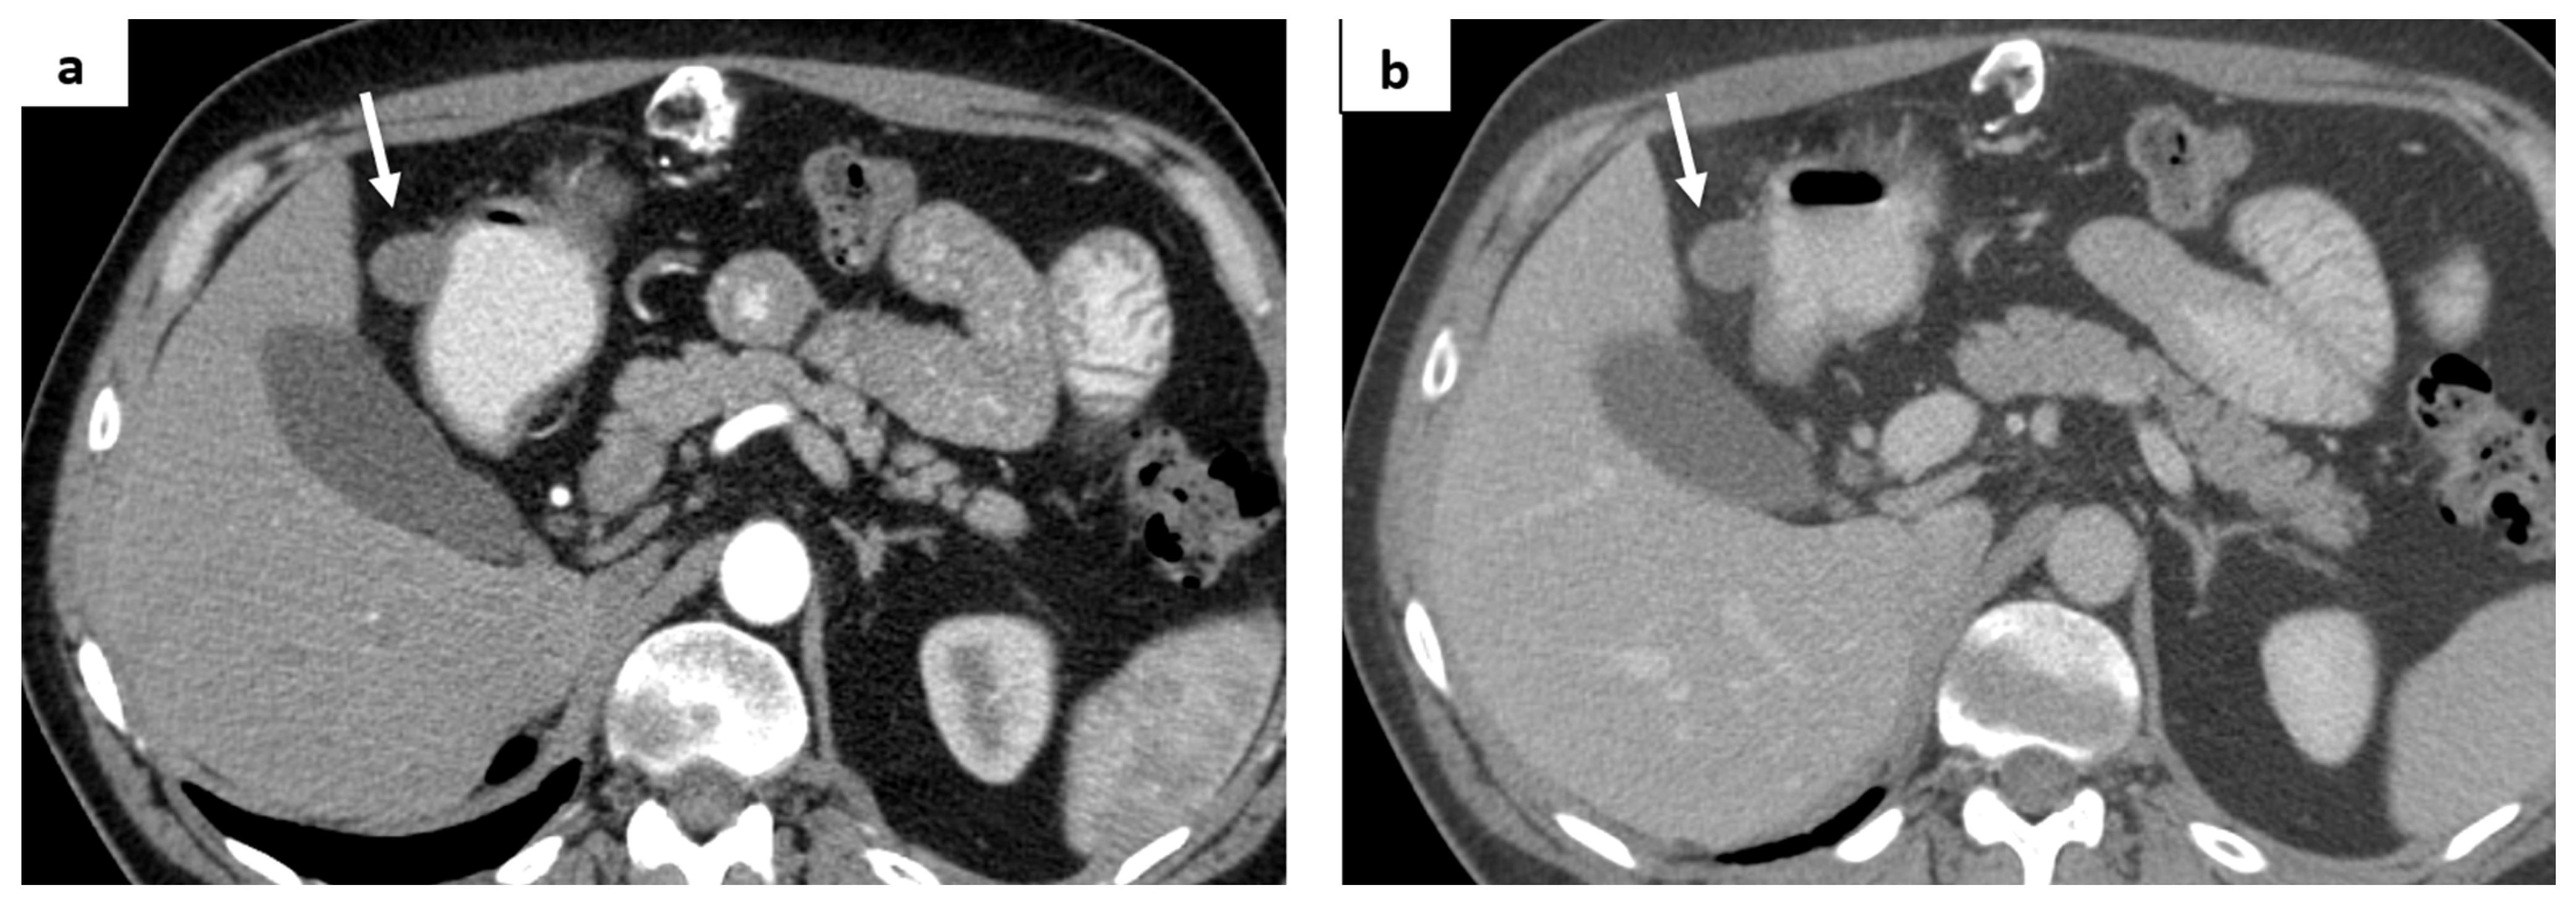

2. Case Report